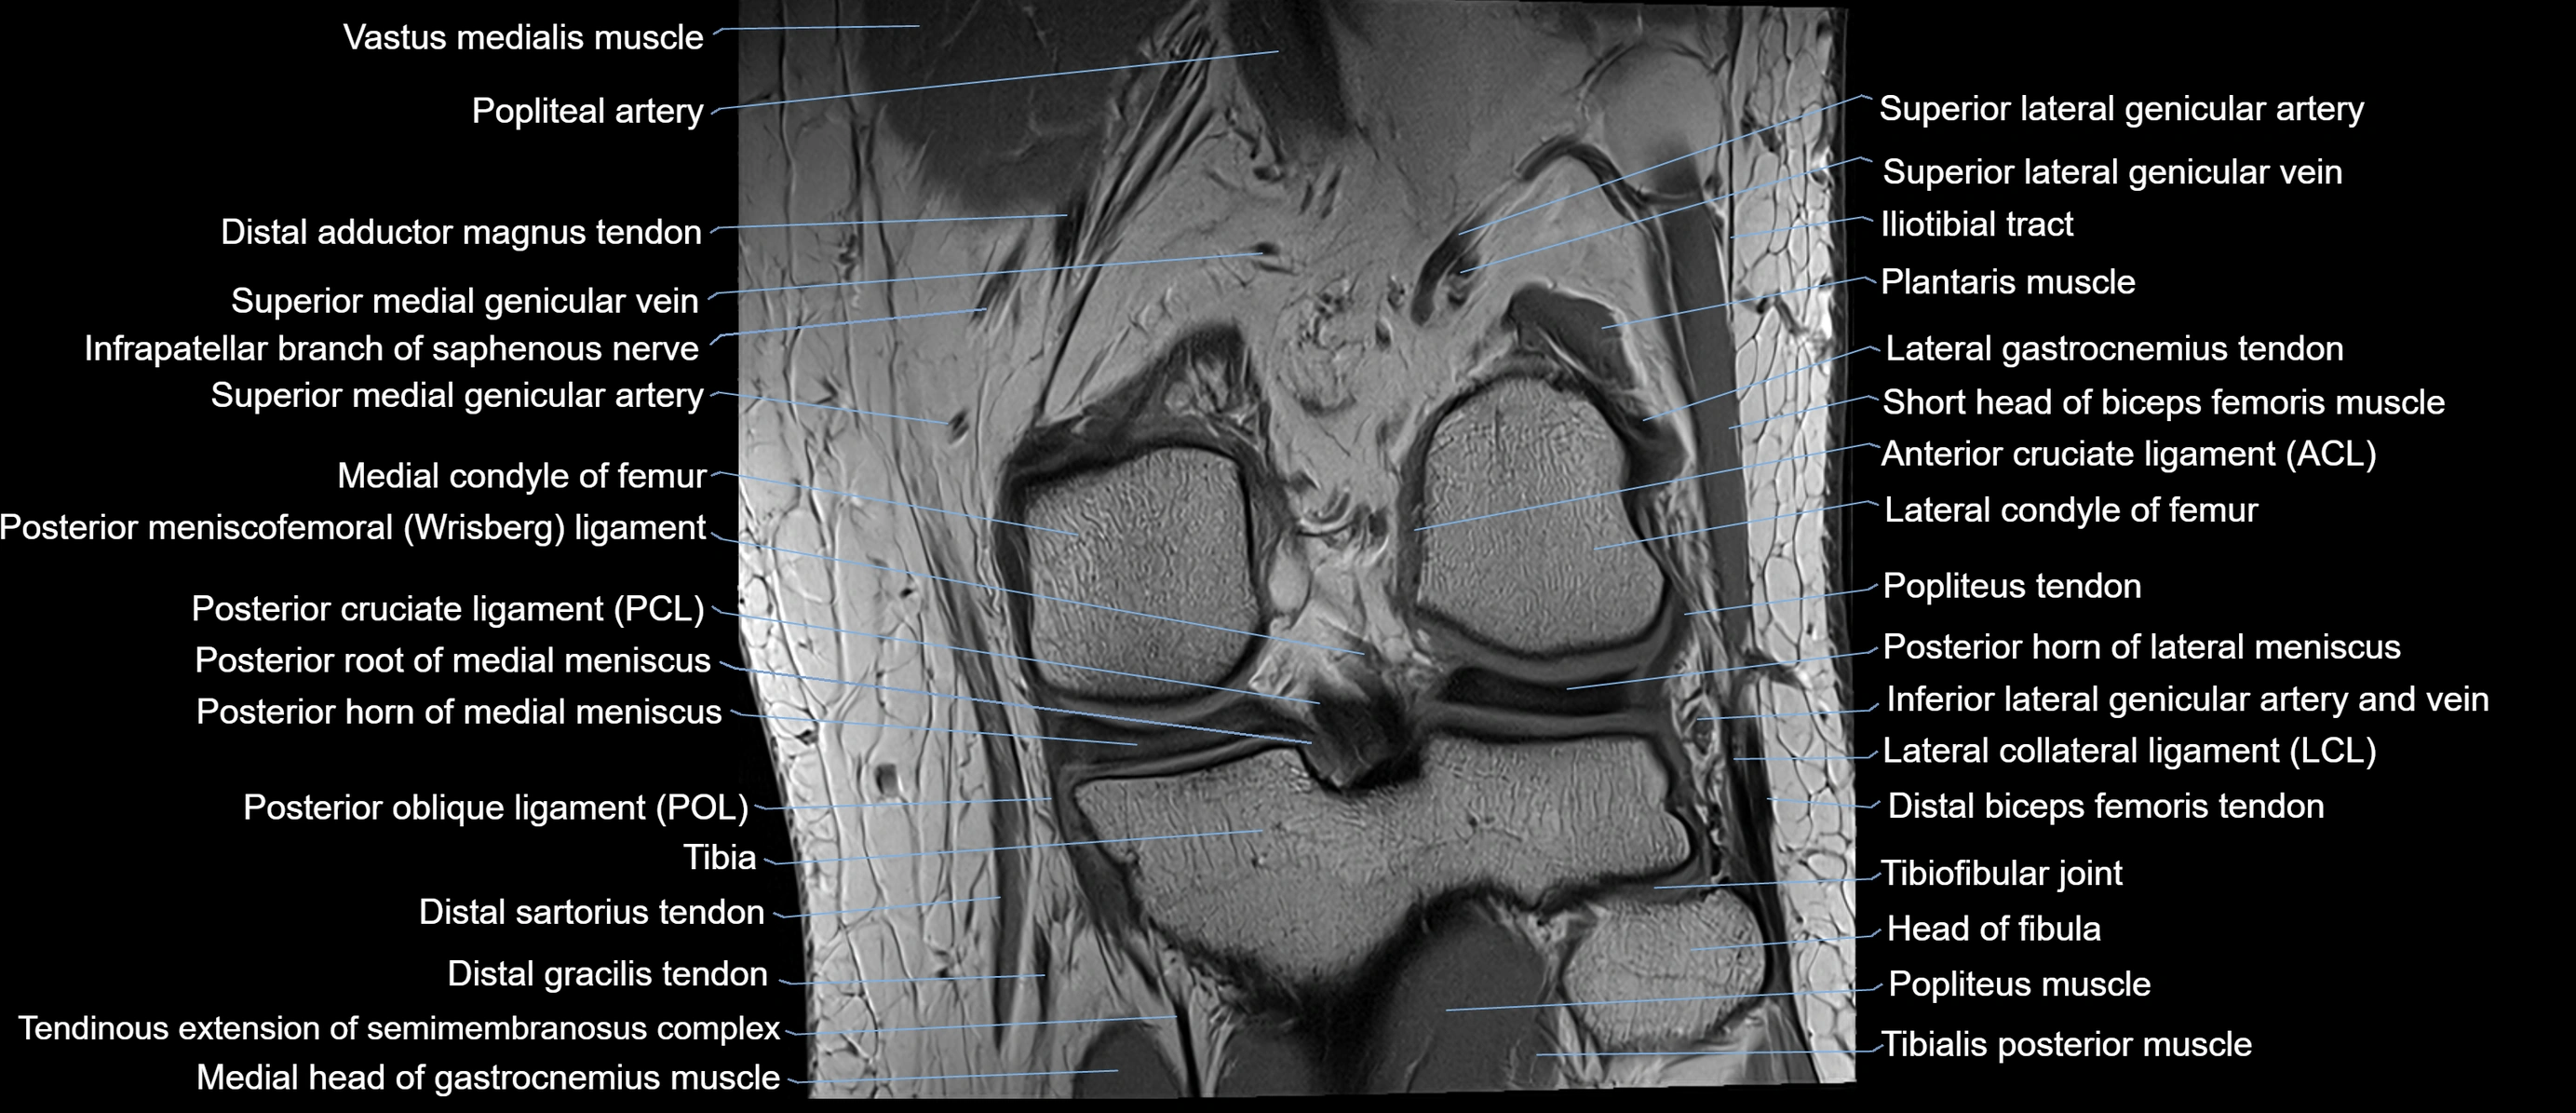

- Anterior cruciate ligament

- Arcuate popliteal ligament

- Body of medial meniscus

- Distal biceps femoris tendon

- Lateral collateral ligament

- Lateral condyle of femur

- Lateral gastrocnemius tendon

- Medial condyle of femur

- Medial meniscus

- Popliteal artery

- Popliteal vein

- Popliteus muscle

- Popliteus tendon

- Posterior cruciate ligament

- Posterior horn of lateral meniscus

- Posterior horn of medial meniscus

- Posterior meniscofemoral ligament

- Posterior root of lateral meniscus

- Posterior root of medial meniscus

- Superior lateral genicular artery

- Superior lateral genicular vein

- Superior medial genicular artery

- Superior medial genicular vein

- Tibia